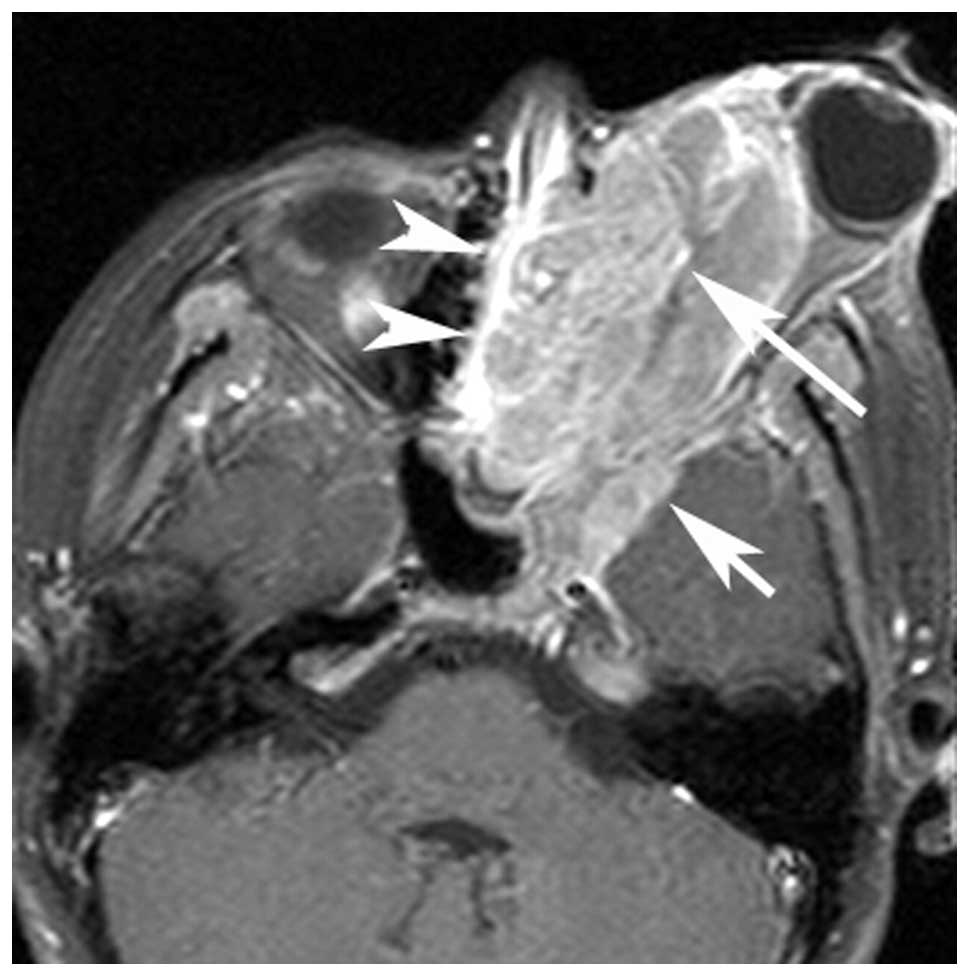

MRI Of Rhabdomyosarcoma And Other Soft-Tissue Sarcomas In Children

pubs.rsna.org

pubs.rsna.org

rhabdomyosarcoma mri embryonal sarcomas rg

Computed Tomography And Magnetic Resonance Imaging Observations Of

www.spandidos-publications.com

www.spandidos-publications.com

rhabdomyosarcoma neck head embryonal axial tomography computed imaging magnetic observations resonance ol figure

Computed Tomography And Magnetic Resonance Imaging Observations Of

www.spandidos-publications.com

www.spandidos-publications.com

rhabdomyosarcoma computed tomography magnetic imaging observations resonance neck head figure ol